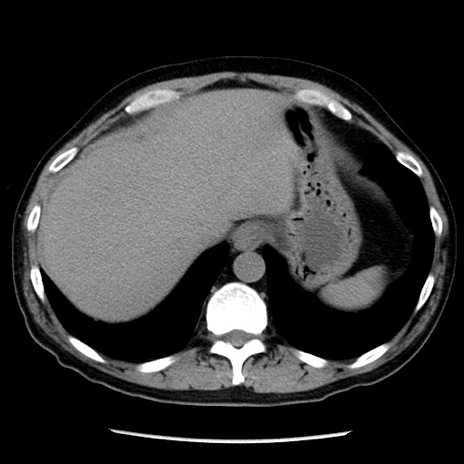

症例29(横断像)

【症例】40歳代男性

【現病歴】2日前から胃痛あり。徐々に周期的な激痛に変化した。本日になっても激痛があるため受診。

【身体所見】意識清明、BT 38-39℃台あり、腹部:膨満、やや硬、右下腹部に圧痛あり。

【データ】WBC 8500、CRP 23.26